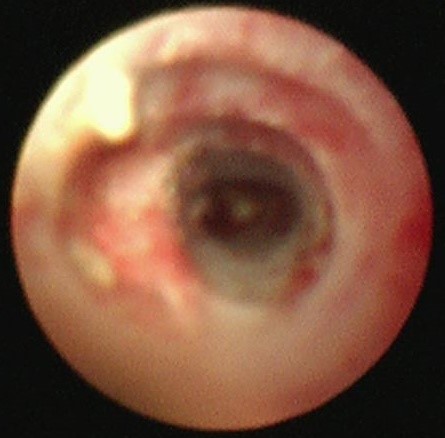

两天后复查支气管镜,发现患者左下叶背段远端细支气管仍有残留泥沙样异物。团队采用超细支气管镜联合冷冻技术,通过冷冻探头将异物凝固,再用超细活检钳逐支清理,实现对远端气道的彻底清理,实现气道“零死角”。

(远端支气管治疗后)